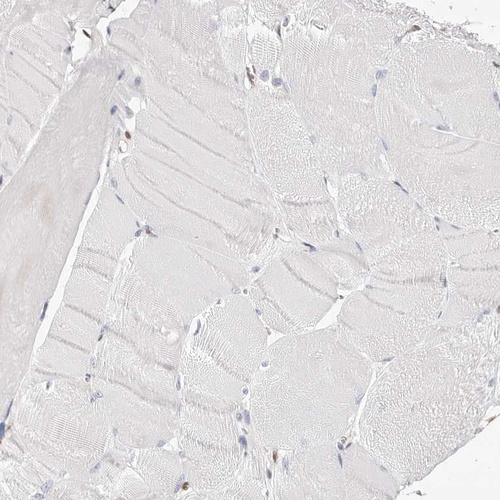

Immunohistochemistry analysis in human bone marrow and skeletal muscle tissues using HPA029480 antibody. Corresponding TKT RNA-seq data are presented for the same tissues.